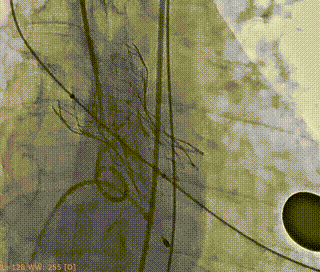

术前造影(左右窦重合体位)

释放支撑臂